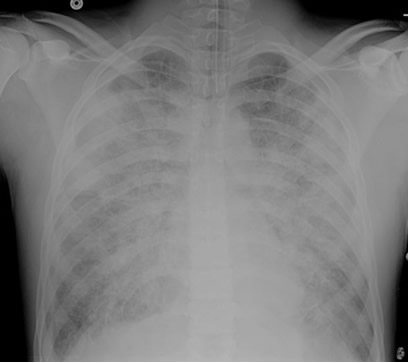

Post-intubation CXR for the case found here:

(CXR source: http://courses.washington.edu/med620/images/mv_c3fig1.jpg)